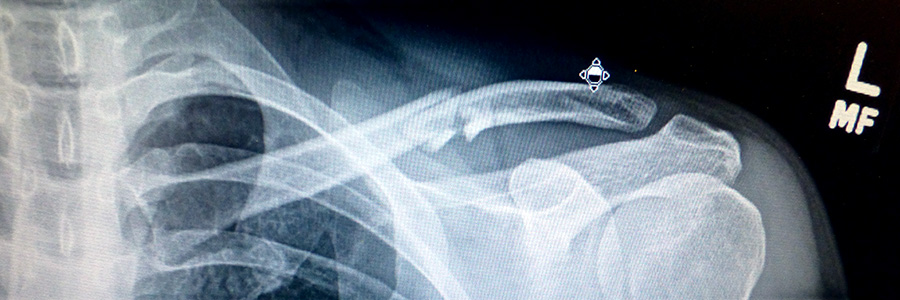

i arrived at 3C yawkey right at 8:30. i took off my jacket in the waiting room. after 10 minutes of waiting an attendant came in and brought me into one of the exam rooms. there was a computer with my x-ray photos (from last week) on the screen. i waited another 15 minutes before a resident came me and asked me to take my shirt off so he could do a quick check of my condition. he left me with some medical forms to fill (kind of weird, given that it should all be in the MGH database already) while i waited for the doctor to show up.

the basic gist of what they said was this: i was healing normally, there seems to be no complications, and i have the full use of my arm, it just depends on how much pain i can tolerate. doctor vrahas said there wasn't anything i could do to stop the healing process. one of my concerns was looking at the x-rays and feeling it for myself, there seemed to be a very large and hard sticking out from the breakpoint, like maybe the bones weren't aligned properly and needed to be set. the doctor told me this was quite normal, that a lump forms around the fracture site, but over time the lump gets reabsorbed and the bone goes back to normal. i still had questions, but it seemed like i had nothing to worry about, with the underlying message that was all very normal. the doctor even pressed down on the lump and i was surprised there was no pain when he did it, because i always felt that spot was still broken, especially since i can move my arm in such a way that i can feel something grinding there. the doctor even said i didn't have to wear my arm sling anymore, unless i wanted to. with that vrahas was on to another patient. the resident stayed behind, asked if i needed help getting dressed. he also added that if i was looking for a perfect place to break a bone and have it heal back to normal, i couldn't have picked a more perfect spot.